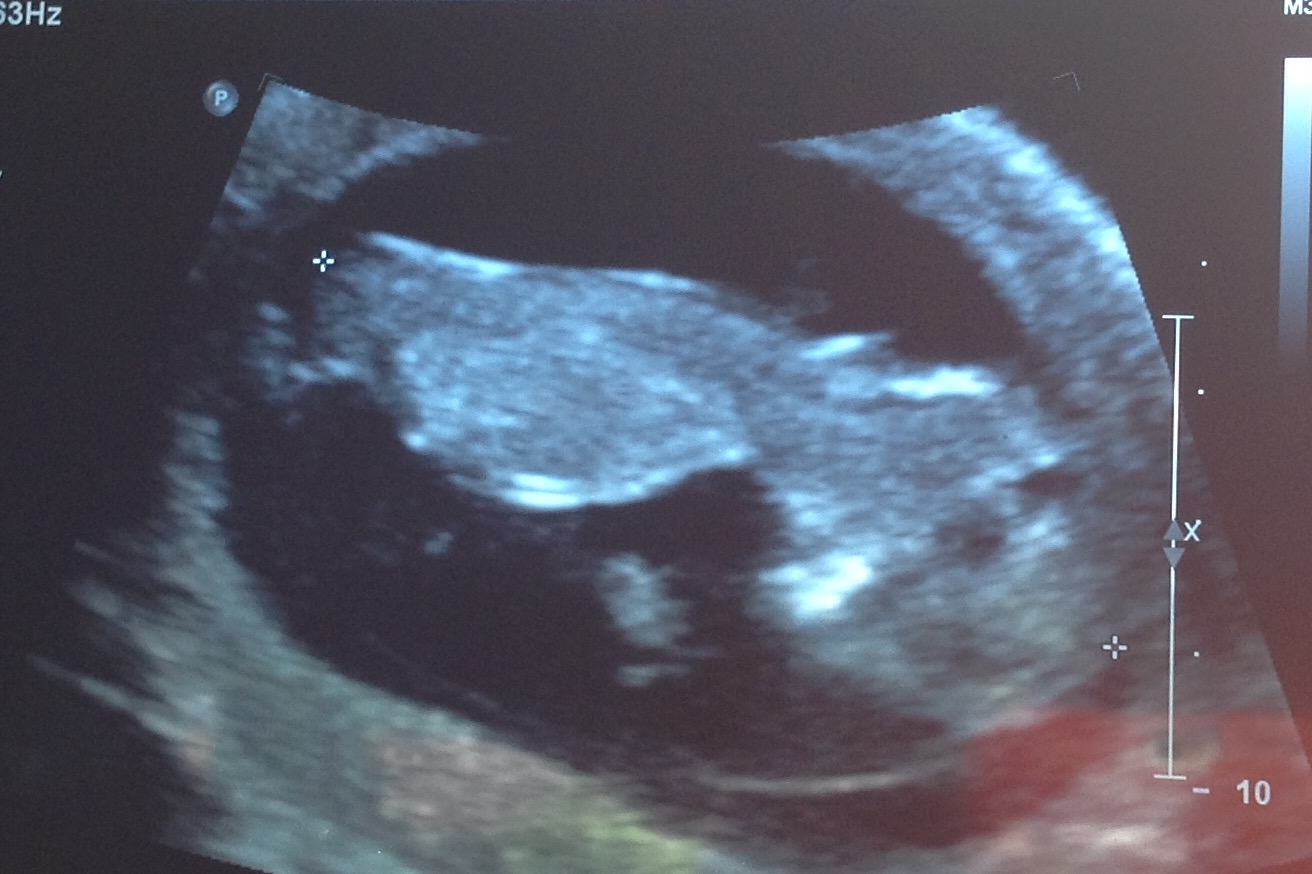

Any chance boy nub could be girl or am I clutching at straws?

I didn't want to know the gender of baby #2 and didn't think I would be able to tell from 12w 3 day NT scan pics so I just peeked at them out of curiosity. It seems very clear that bub has a typical boy nub - virtually sticking straight up and stacked. Is there any chance I could later be told girl or none whatsoever? I am thinking it is impossible this is my longed for DD and should just accept this but just wondered if anyone else has been told 100% boy or seen very boy nub but had a girl. Think I need to give up hope but I am just having a hard time especially as I really didn't want to know this early.